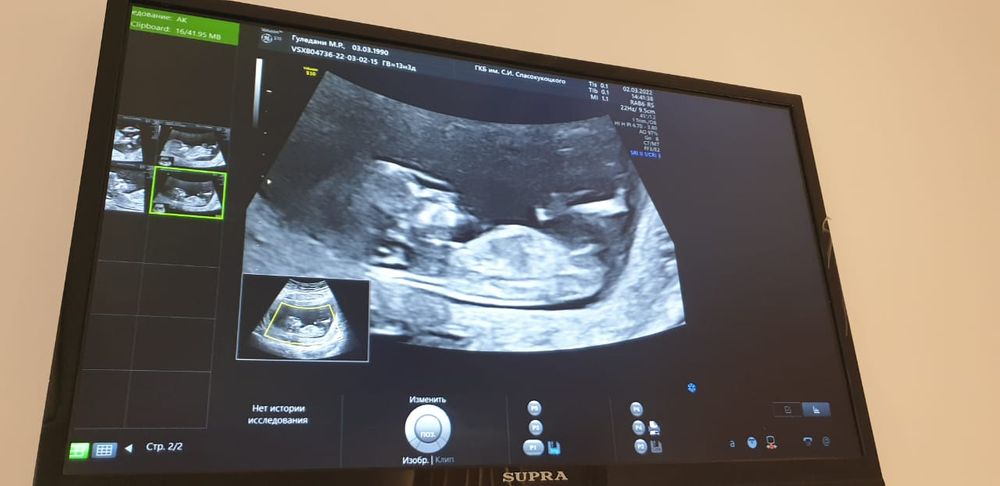

По 1 фото сразу виднеется мальчик, но это скорее пуповина, на 2 и 3 фото девочка)))

РоМаШка, вот и врач сначала предположила девочку, а потом засомневалась и сказала, что пока непонятно) тут все за пацана проголосовали 😁

Я больше на девочку склоняюсь, но первое фото на мальчика похоже

Мечты сбываются , вот из-за первого фото все думают, что мальчик) 🙈 посмотрим, действительно ли это писюн или пуповина 😁😁

Мальчик конечно, для девчачьего отросточка сильно толстоват и машонка есть, как тут можно девочку предположить😂🙈

Christina, эти фото сделаны на 1 скрининге в 12,1 неделю) врач предположила тогда, что девочка) но тут все единогласно за мальчика😅 Сейчас уже 18я неделя идет